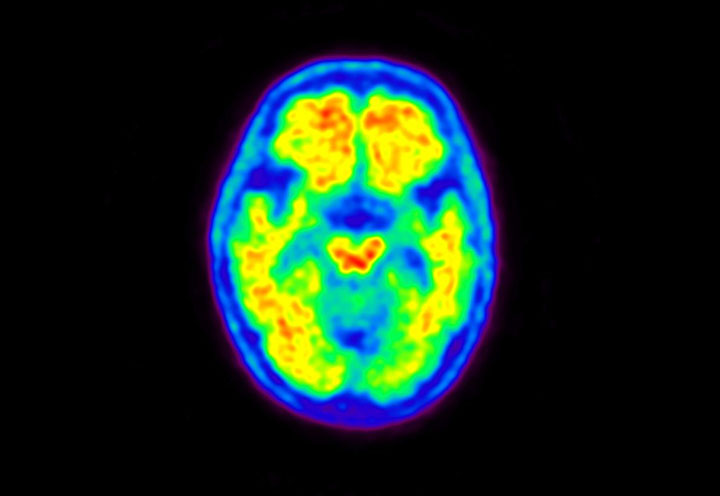

Head / Case5 : Amyloid

Courtesy : Kindai University Hospital

- Imaging protocol

- Injected dose: 4.27 MBq/kg, 18F-Flutemetamol

- Uptake time: 99 minutes

- Scan time: 20 minutes